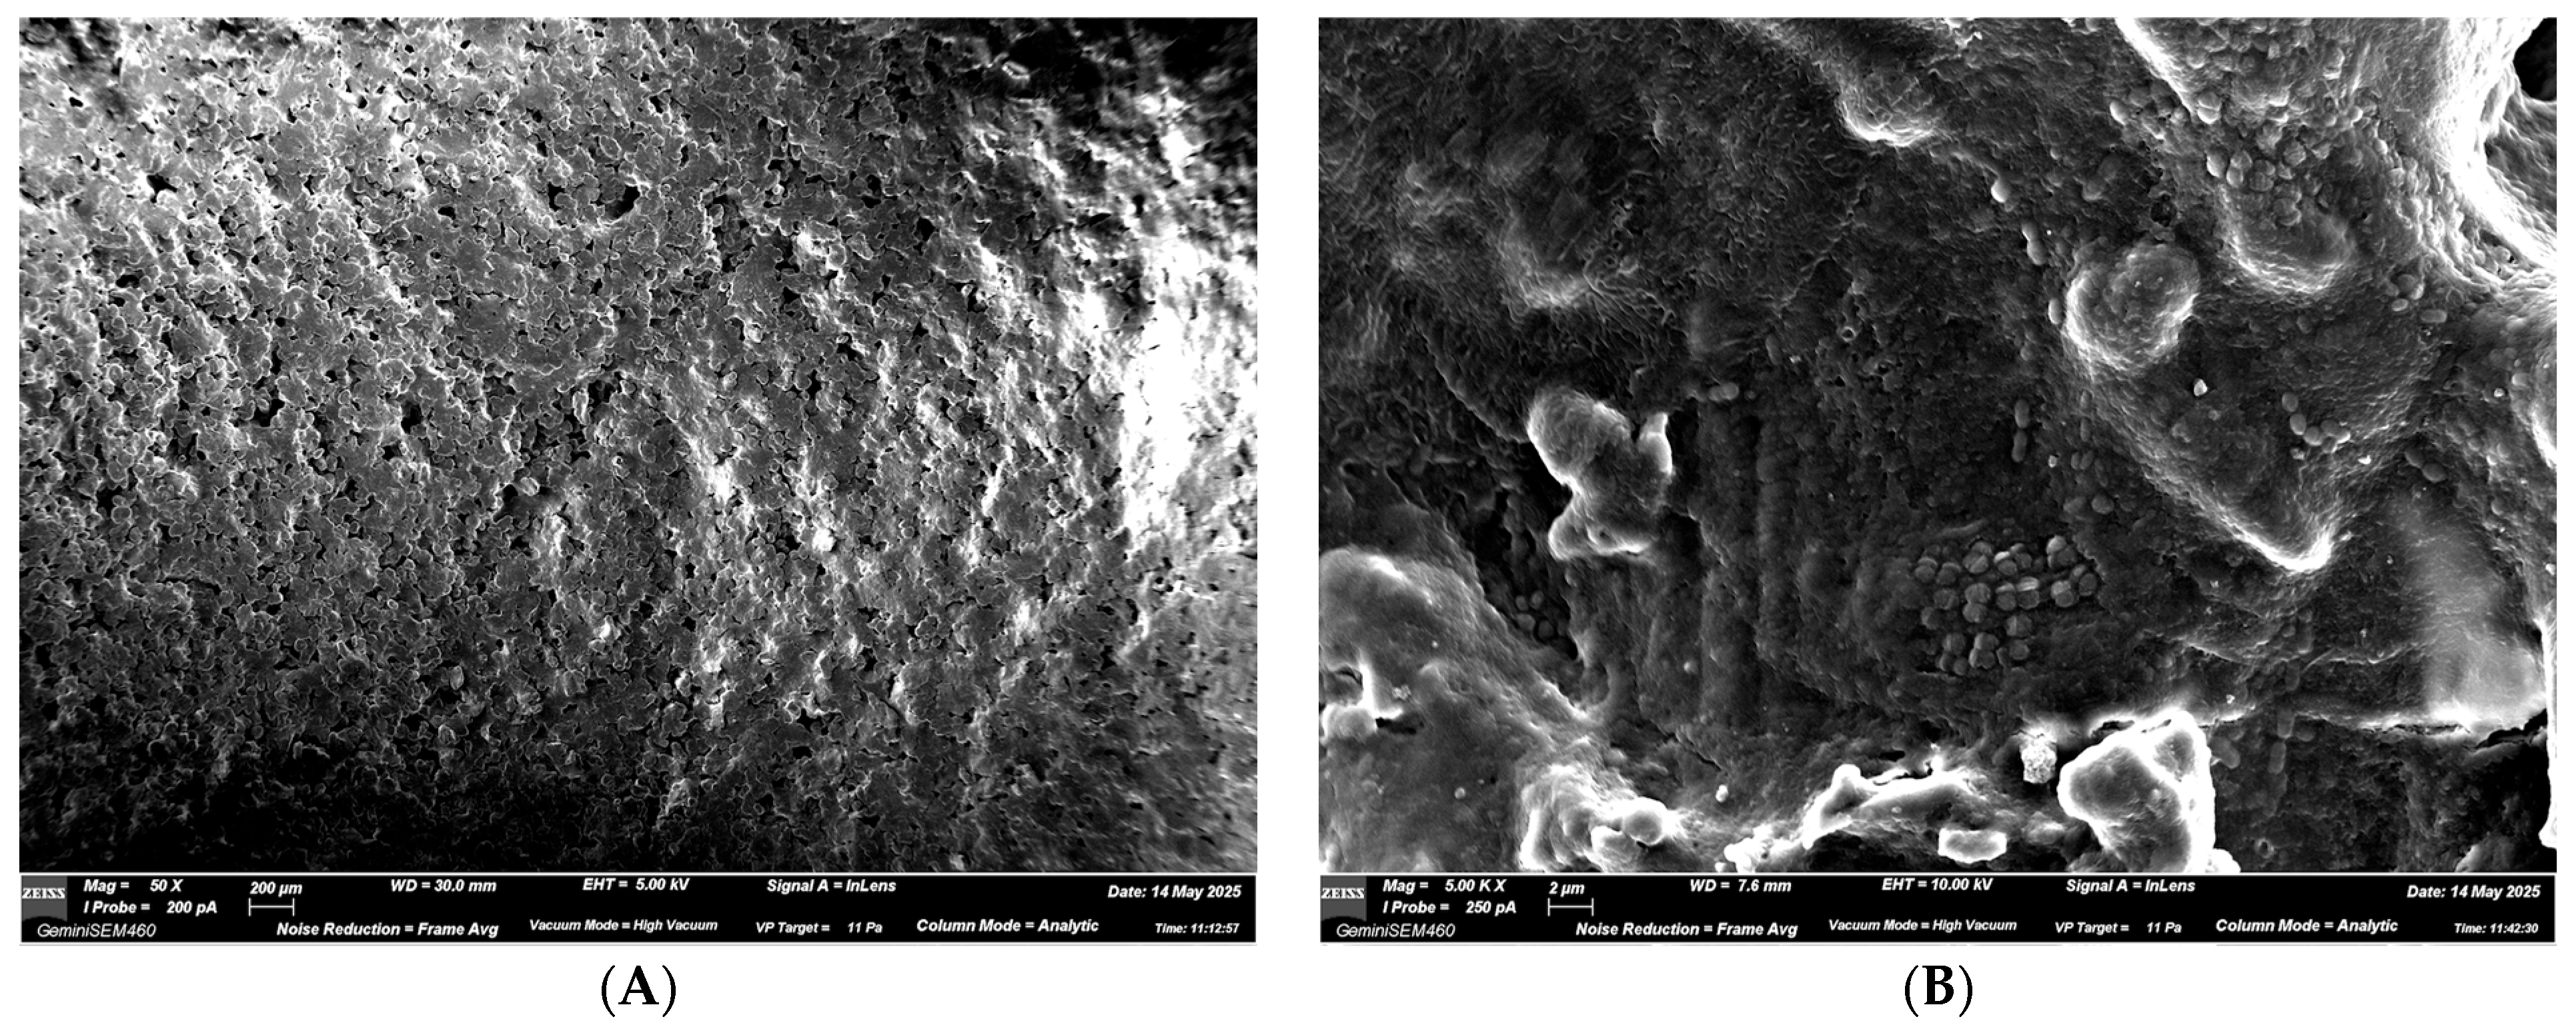

3.2.2. ALIGNER B—USED Aligner Without Spray

- Aligner B (used 14 nights without spray);

- USED aligner worn for 14 nights without spray;

- Increased deposition was defined as continuous organic layers, confluent bacterial aggregates, or dense clusters covering the underlying polymer texture.